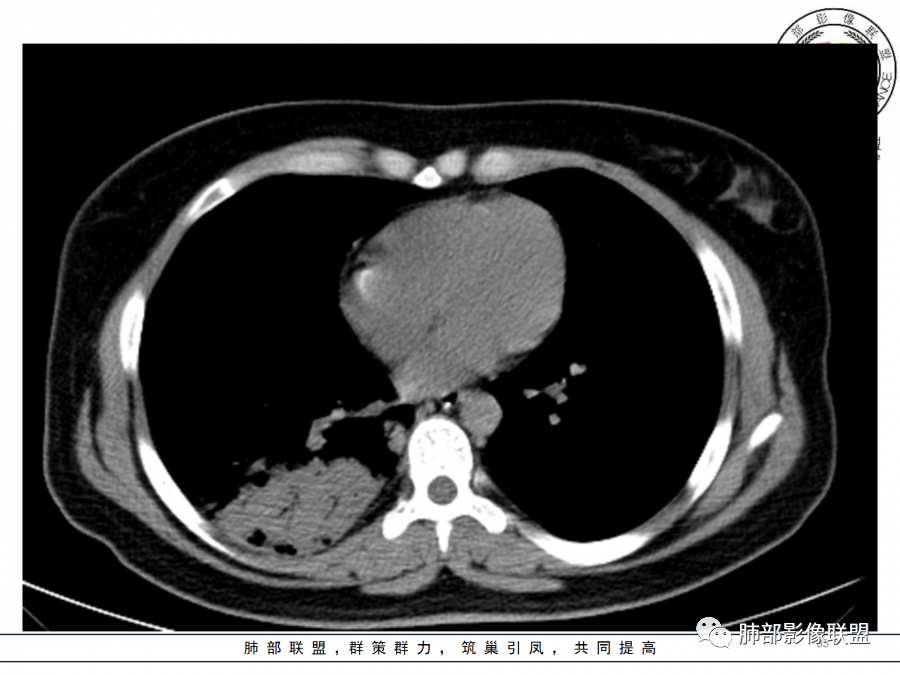

4)病灶体积增大明显(叶间裂推移)。

4.隐球菌感染可以符合上述改变:胸膜下多中心实变密度为主,磨玻璃晕等。但隐球菌临床症状大多隐匿、迁延,影像变化缓慢。

5.本例患者血象高,影像渗出明显,尚不能排除混合感染可能。